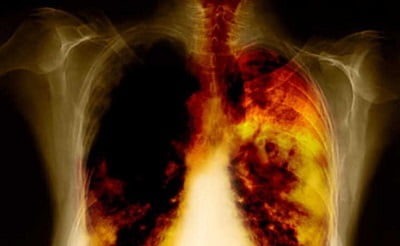

Бронхит курильщика — отдельное заболевание со специфическими симптомами и лечением, которому подвержены как те, кто имеет вредную привычку курить, так и лица, вдыхающие сигаретный дым пассивно. Очень часто недуг приобретает хроническую форму. Постепенно ослабляя иммунитет, влияя на дыхательную функцию, он может повлечь за собой весьма негативные последствия для здоровья.

Основным симптомом болезни является кашель. Если лечением бронхита курильщик пренебрегает, кашель может перейти в хронический. Просветы бронхов сузятся, вырабатываемая слизь перестанет отходить, содержащаяся в ней патогенная флора начнет активно развиваться, провоцируя постоянные воспаления органов дыхания. Хронический бронхит курильщика может вызывать серьезные последствия: сердечную недостаточность и эмфизему легких.